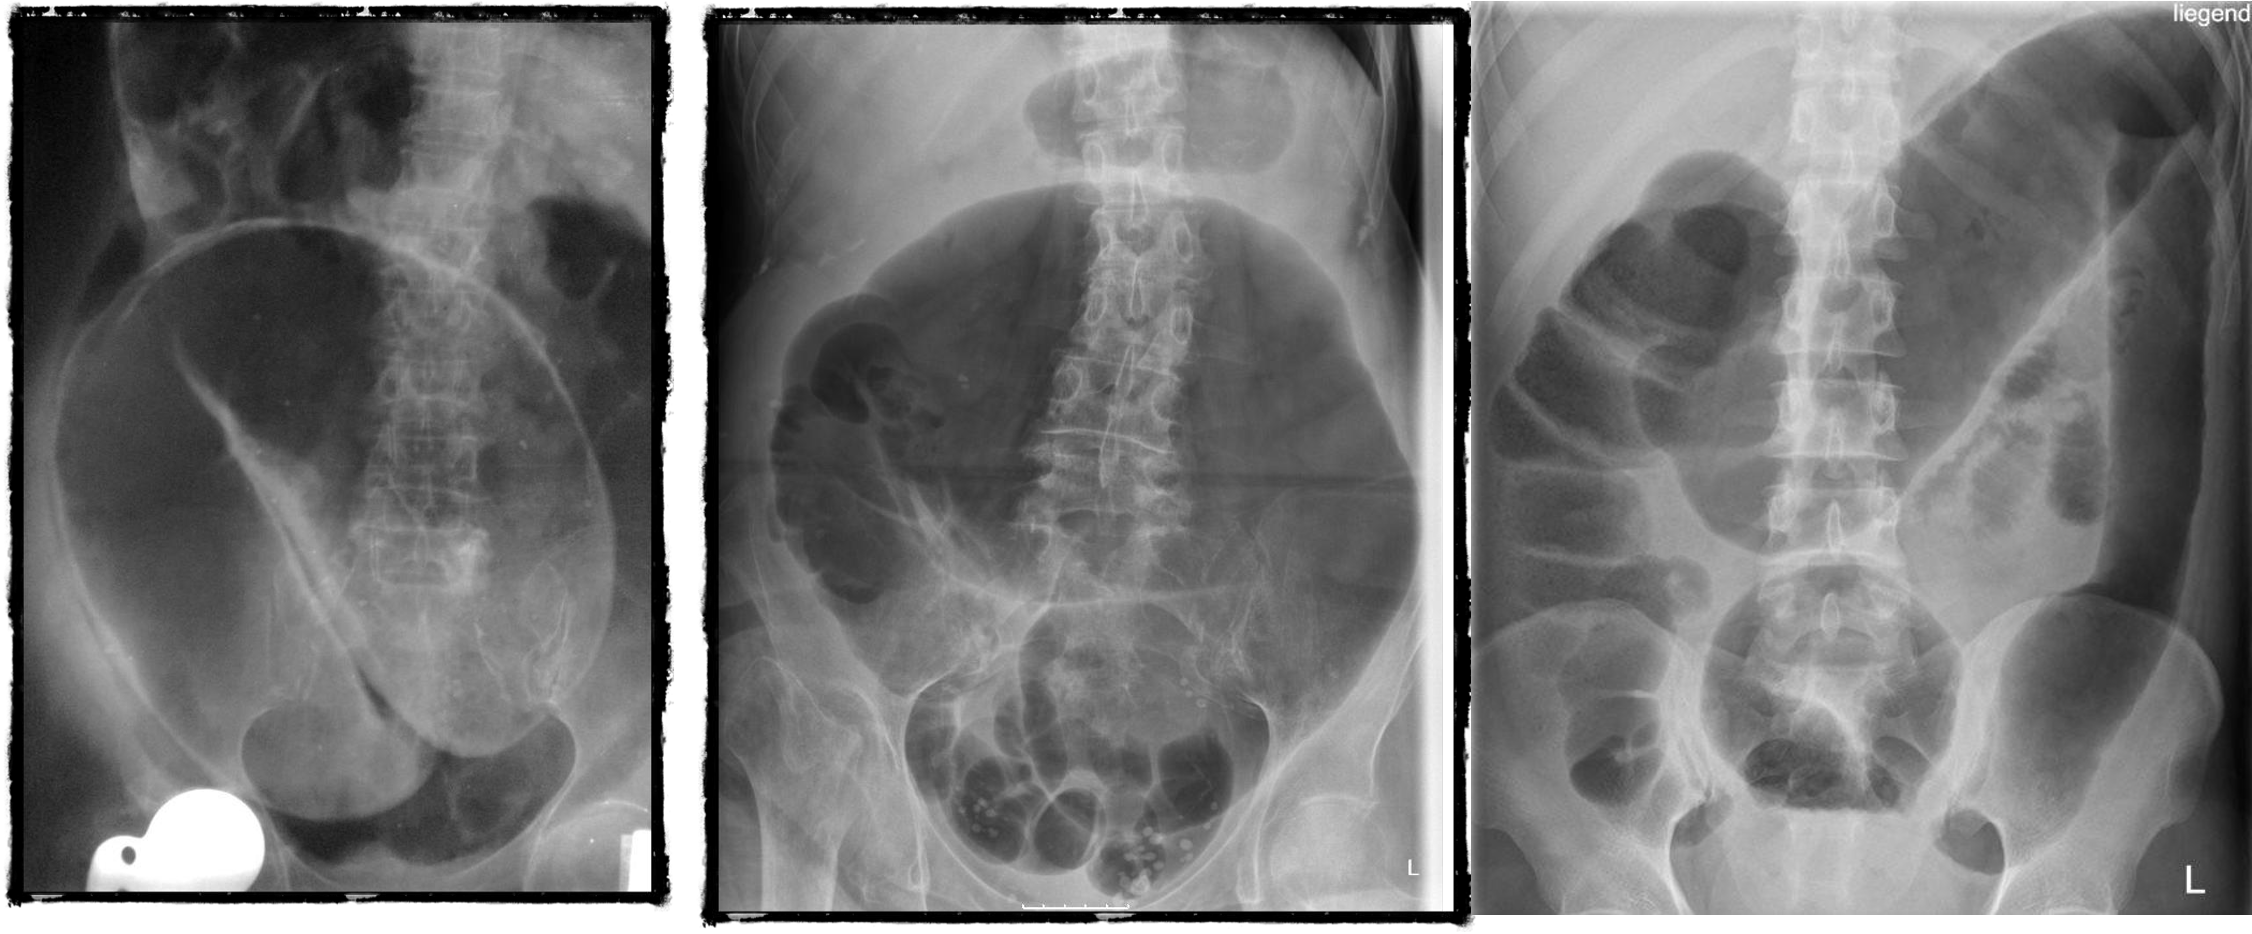

2) Dilated bowel (diff; cancer colon) -

closed loop obstruction from both sides result large bowel most dangerous left side most common cancers

- coffe bean - omega sign - volvulus twisting around its axis - it is closed loop obstruction very dangerous - (treat clonoscopy decompression)

- volvulus

- abdominal x-ray - Dilated colon (diff - cancer colon, ulcerative colittis)

- 8 air fluid - small intestinal central - intistinal obstruction due adhesion - stack of coins. ++ NG tube aspiration relieve from vomitting

- dilated small bowel obstruction - stack of coins

- small bowel

2) large bowel - mucosal issnt complete periphery